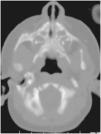

Durante el segundo ingreso se le realizó una TC de las fosas nasales en la que se observó la disminución de la distancia entre ambos procesos nasales del maxilar (fig. 1), incisivo central único congénito (fig. 2a y b) y paladar triangular (fig. 3) con cresta central (fig. 4), hallazgos compatibles con ECOP.

El diagnóstico definitivo de la ECOP se realiza mediante TC de las fosas nasales. Los hallazgos radiológicos consisten en un crecimiento excesivo del proceso nasal del hueso maxilar, un paladar duro hipoplásico con morfología triangular (fig. 3) y un consecuente estrechamiento del orificio piriforme (fig. 1).

La paciente que aquí se presenta cumplía con estos hallazgos descritos. Asimismo, presentaba una pequeña cresta ósea en la línea media por debajo del paladar duro en la reconstrucción coronal (fig. 4) y un gran diente incisivo único central (fig. 2). Éstas son alteraciones típicamente asociadas a la ECOP; es particularmente destacable la alteración de la dentición, ya que el megaincisivo central único puede ser una manifestación de la holoprosencefalia, por lo que se indica un estudio de imagen cerebral, preferiblemente una resonancia magnética (RM)1,4,6. En el presente caso se realizó ecografía y RM cerebral, que no mostraron alteraciones.